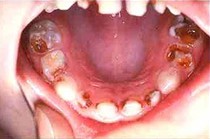

Artritis cura con Bórax  Dolores

de articulaciones por artritis curan con Bórax  Osteoporosis cura con bórax  Caries

es reducica con bórax

Artritis cura con bórax [3] - dolores de articulaciones por artritis curan con bórax [4] - osteoporosis cura con bórax [5] - caries es reducica con bórax [6] -